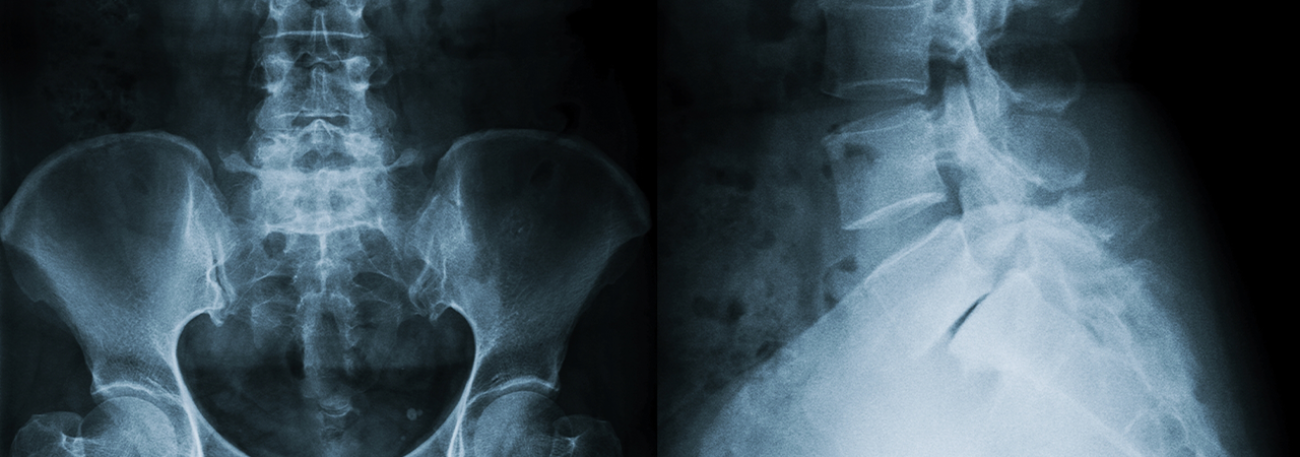

Unsere klinisch orientierte Radiologie präsentiert eine vielfältige Palette an bildgebenden Untersuchungen.

Hierzu gehören Röntgenaufnahmen, Computertomographie (CT), Magnetresonanztomographie (MRT), Ultraschall und mehr. Mit modernsten Geräten ermöglichen wir präzise Diagnosen. Unser erfahrenes Radiologenteam setzt sich für eine schnelle und optimale Bildqualität ein, stets unter Berücksichtigung minimaler Strahlenbelastung. Die enge Kooperation mit Zuweisenden und internen Fachabteilungen gewährleistet eine nahtlose Versorgung. Unser Ziel ist es, rasche Ergebnisse für eine effektive Behandlungsplanung bereitzustellen. Individuelle Betreuung steht bei uns im Fokus, um den Bedürfnissen jedes Patienten gerecht zu werden. Vertrauen Sie auf modernste Technologie und Expertise für erstklassige Radiologie.

Digitales Röntgen

Sämtliche konventionelle Röntgenaufnahmen führen wir in digitaler Technik durch, inklusive Thorax-, Abdomen und Skelettaufnahmen. Die Röntgendokumentation erfolgt ebenfalls digital.

Das Angebot umfasst sämtliche konventionellen digitalen Röntgenaufnahmen für Thorax-, Abdomen- und Skelettaufnahmen, Ultraschalluntersuchungen für Weichteile, Ganzkörper-Computertomographie und MRI-Untersuchungen.